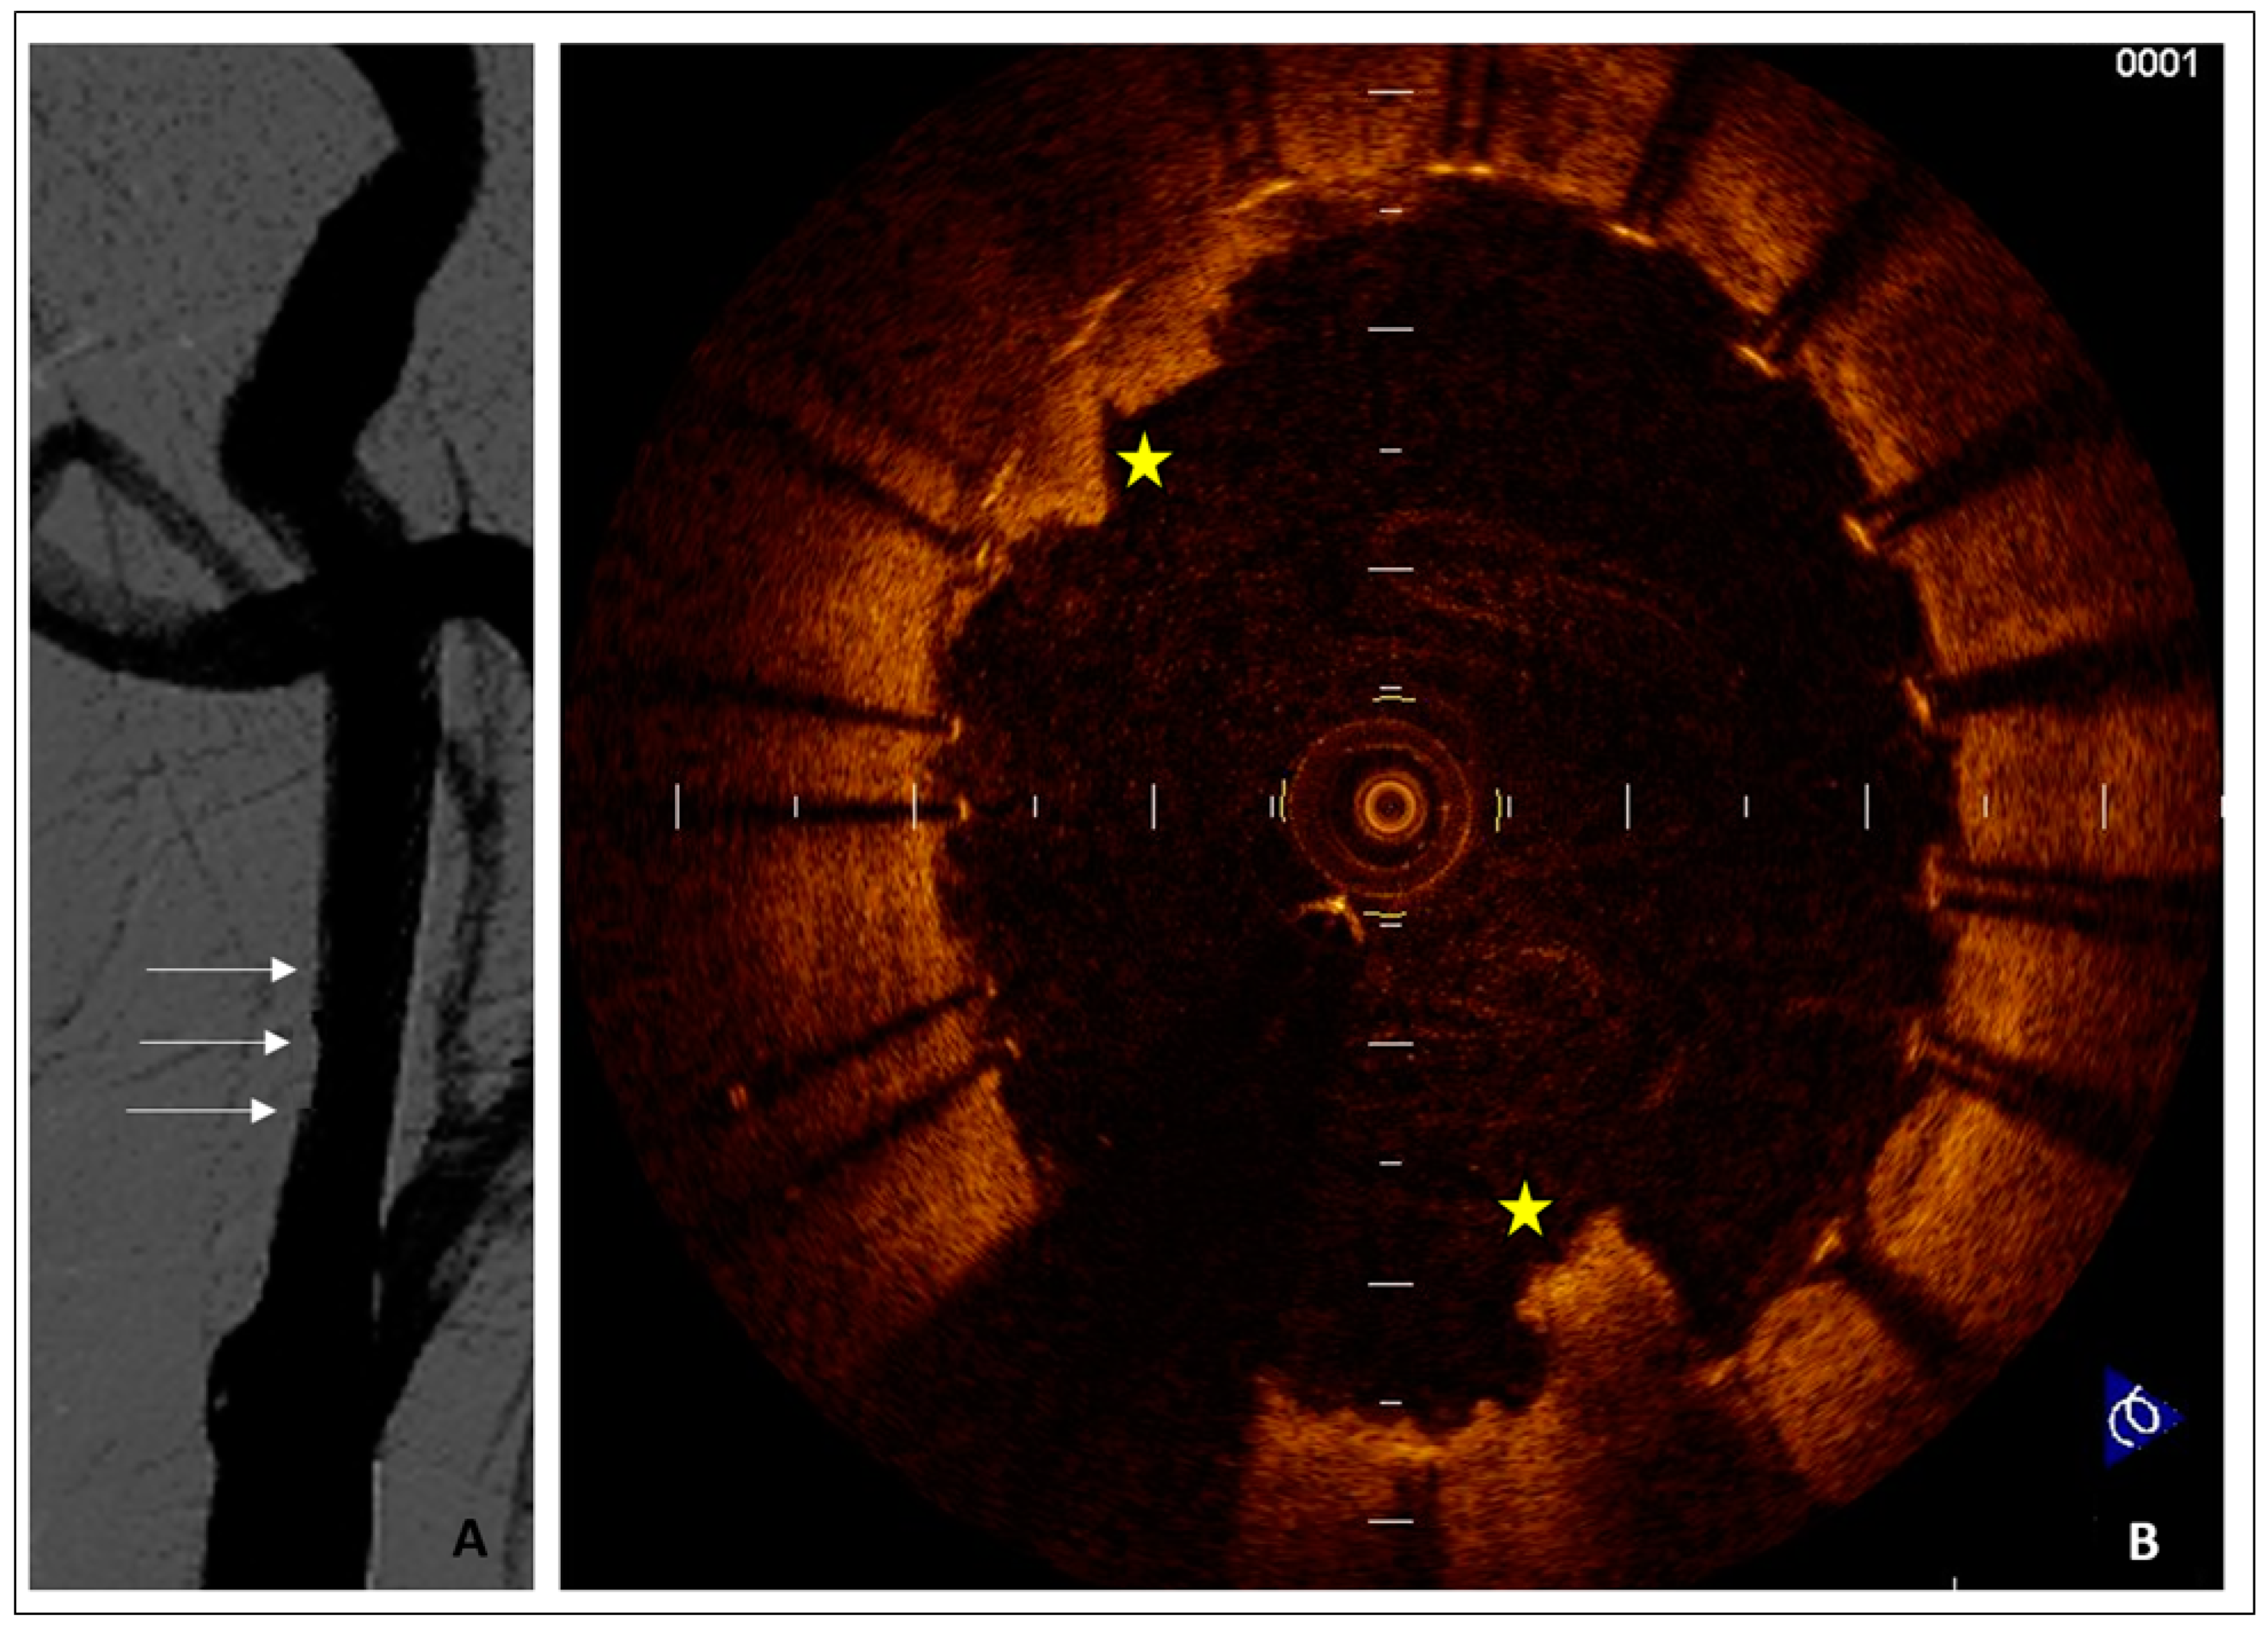

- Plaque prolapse after carotid stenting

- Brief case description